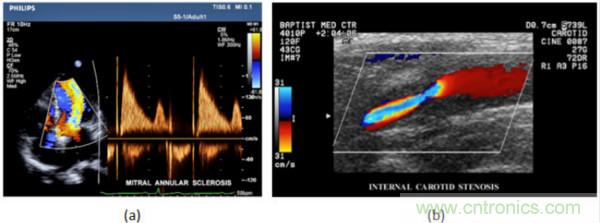

在CW和PW多普勒模式中,流信息是從一個聚焦聲束中獲得的,類似于A模式成像。在20世紀(jì)80年代,研究人員基于彩色多普勒技術(shù)完成了血流分布的二維信息可視化。彩色多普勒處理也是基于B模式/PW模式信號路徑。從感興趣區(qū)域收集多幀RF數(shù)據(jù)。由于感興趣區(qū)域中的血液流動導(dǎo)致圖像幀之間存在數(shù)據(jù)差異。相域中的自相關(guān)和時域中的互相關(guān)兩種算法可從RF數(shù)據(jù)中提取數(shù)據(jù)方差(即血流速度和方向信息):。根據(jù)預(yù)定義的顏色漸變條相應(yīng)地映射包括速度和方向的血流信息。通常,藍色和紅色代碼分別識別朝向和遠離換能器移動的血流。當(dāng)流速增加時使用更亮的顏色,反之亦然。顏色映射的2D分布始終疊加在B模式圖像上,以實時同時顯示個體解剖結(jié)構(gòu)和血流。它對于診斷心血管疾病,如血管閉塞和心臟瓣膜反流,極其有用。典型的彩色多普勒圖像如下圖所示,(b)顯示頸動脈狹窄引起的血流流速變化。

圖7.彩色多普勒成像:(a)以彩色多普勒和CW模式獲得的圖像(由Philips提供); (b)顯示頸動脈狹窄的彩色多普勒(由GE提供)